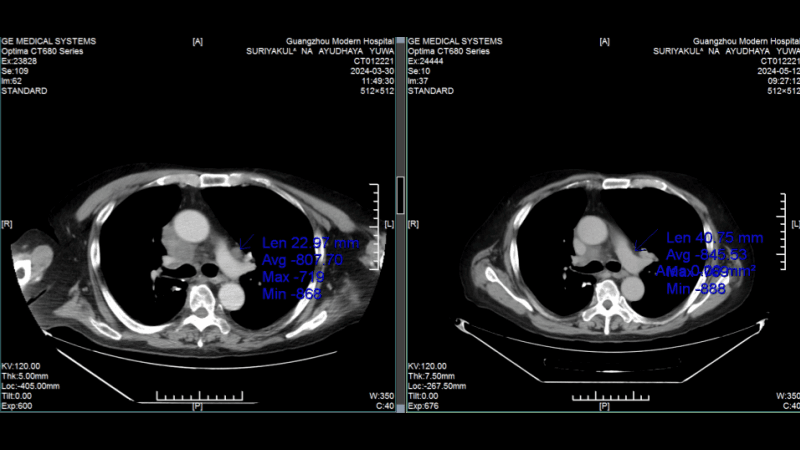

Малоинвазивная интервенционная терапия помогла победить синхронный рак легкого и колоректальный рак, когда хирурги всего мира предлагали только калечащие операцииИстория пациента: Радик, 63 года, Россия. Диагноз: Два первичных очага: плоскоклеточный рак легкого и аденокарцинома прямой кишки (синхронный рак). Тактика лечения: Курс интервенционной терапии (химоэмболизация). Результат: Очаг в легком практически неактивен, опухоль в кишечнике уменьшилась на 90%. Полное восстановление качества жизни.

Сравнение КТ лёгких до и после лечения. Опухоль лёгких практически инактивирована

(Слева: до лечения, справа: после лечения)

Лечение дало ошеломляющие результаты: • После двух процедур КТ показало уменьшение очага в легком, а колоноскопия - значительное сокращение опухоли в кишечнике. • Исчезли мучительные симптомы: кашель и кровавый стул. • После семи сеансов опухоль в легком была практически полностью инактивирована, а в кишечнике - уменьшилась на 90%. Путь не был усыпан розами. Однажды у Радика резко упал уровень тромбоцитов, что грозило опасным кровотечением. В момент отчаяния именно настойчивость и профессионализм его лечащего врача, доктора Аденана, и всей команды спасли ситуацию. Быстро проведенная симптоматическая терапия стабилизировала состояние, и лечение было продолжено.